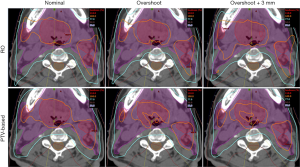

For better illustration of sensitivity to range and setup uncertainties, we compared the dose distributions in transverse plane. Figure 1 is the comparison result of one lung case. Left panels are dose distributions in nominal position; the middle panels are corresponding data with +3.5% over-range, and the right panels are for +3.5% over-range plus 5mm shift in all directions. The underdose regions appeared in the scenarios of overshoot and displacement by using PTV-based optimization, whereas the target remained better dose coverage in the RO plan. This result demonstrates the insensitivity of the RO plan to proton uncertainties compared with the PTV-based optimized plan.

Figure 3 and Figure 4 show the transverse dose distribution and DVH for one head-and-neck case. The dose distribution in the RO plan was insensitive to range and setup uncertainties compared to PTV-based plan. The DVH bands of target was narrower for the RO than PTV-based plan. The sigma value was also smaller which indicates the plan has less response to proton uncertainties. Both the head-and-neck and lung cases showed similar results.